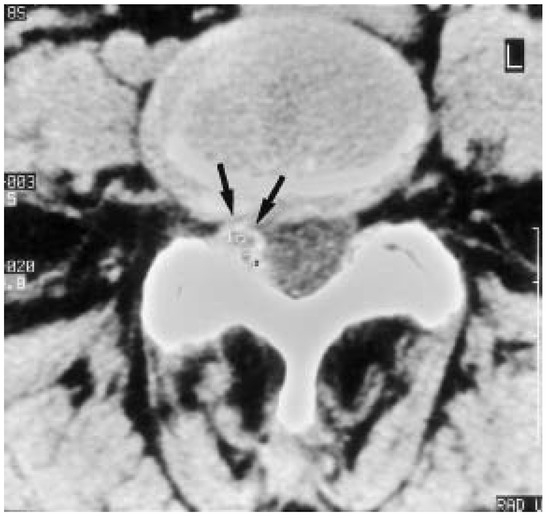

Seltene Ursache einer hartnäckigen Ischialgie

by S. Rüegg, O. Gratzl and A. J. Steck

Swiss Arch. Neurol. Psychiatry Psychother. 1999, 150(4), 189-191; https://doi.org/10.4414/sanp.1999.01105 - 1 Jan 1999

Viewed by 33 Show Figures

Figure 1